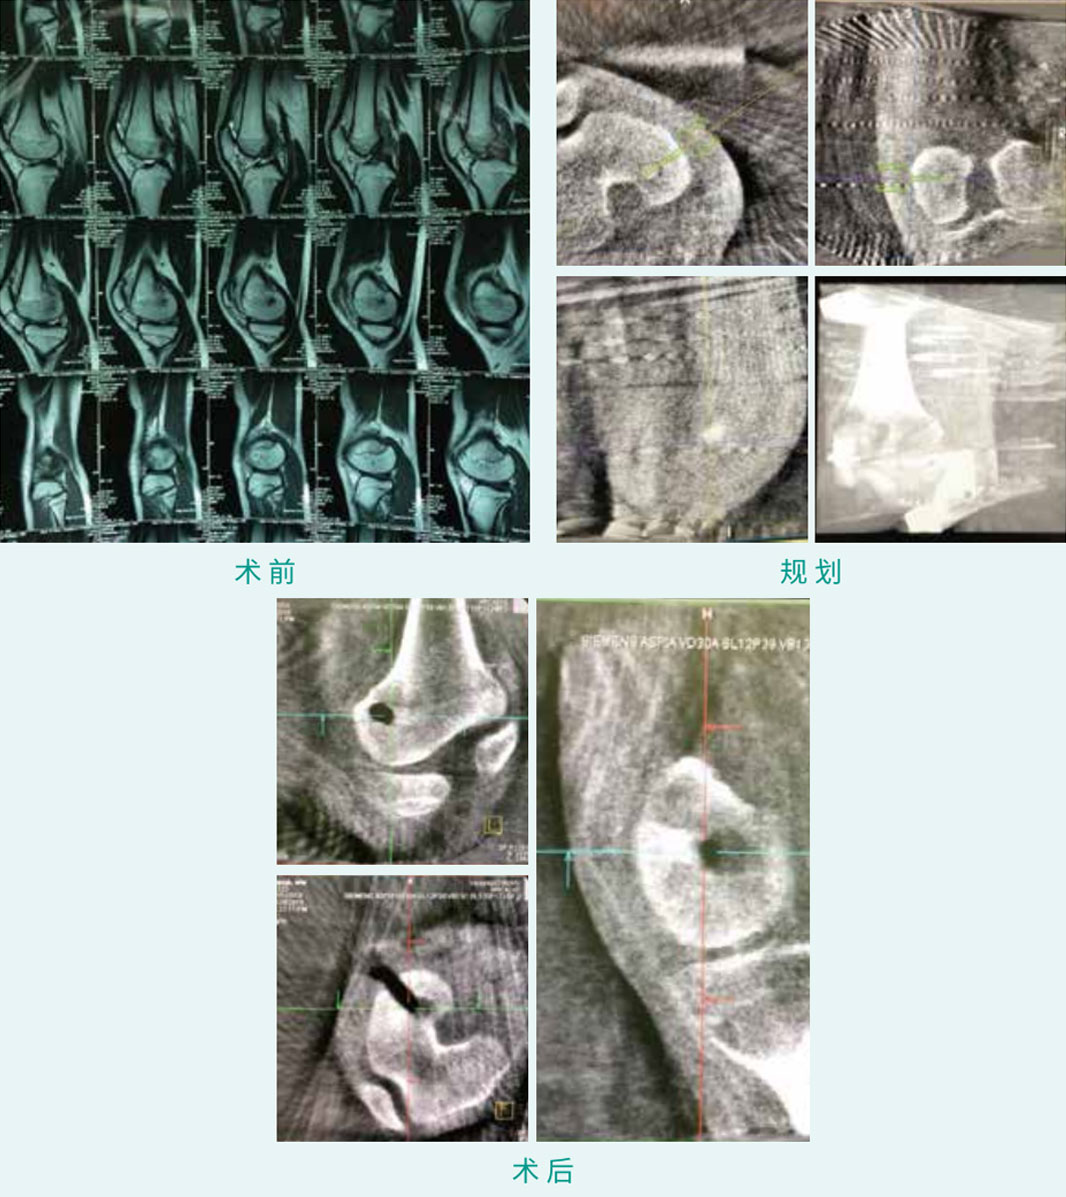

股骨髁骨肿瘤指导

TiRobot ?  Femoral Condyle Tumor Location

天玑? 辅助股骨髁骨肿瘤指导

基本情形:患子女,13岁,股骨髁骨肿瘤

机械人累积用时:20分钟

病例泉源:佛山市中医院 劳永锵